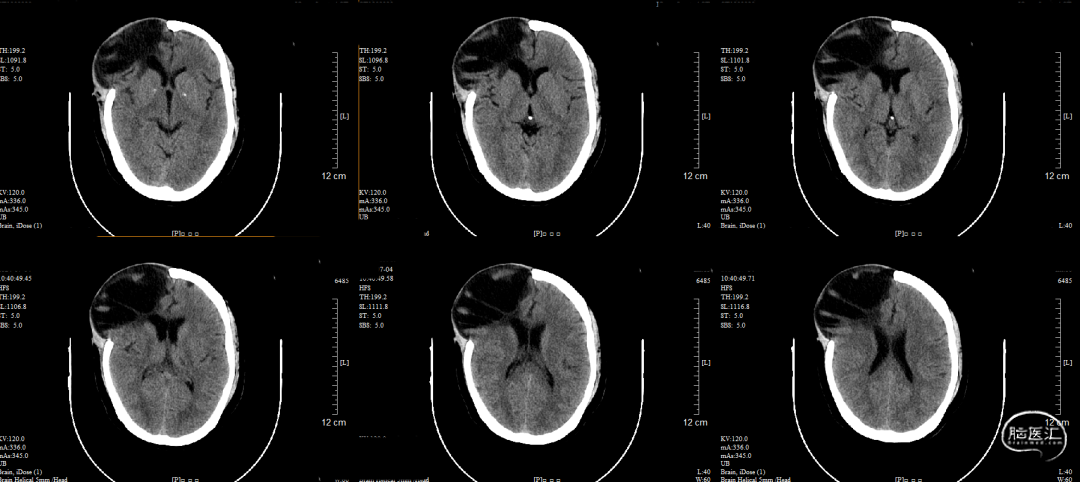

术前CT

额部脑组织软化、局灶性脑积水,膨出骨窗